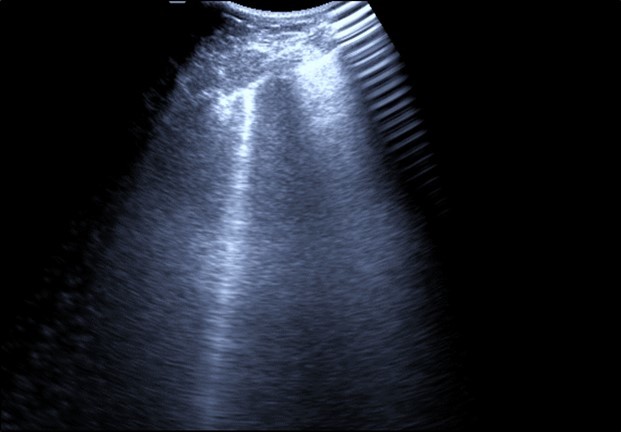

Bed side chest ultrasound may reveal positive findings as multiple Kerley’s B lines (>3 per intercostal space), pleural wall thickening (Figure 1), patchy areas of pulmonary consolidations especially in subpleural location (Figure 2, Figure 3) and obstructive lung collapse.

Figure 1.Real time chest ultrasound showing Kerley’s B lines in patient with covid -19.